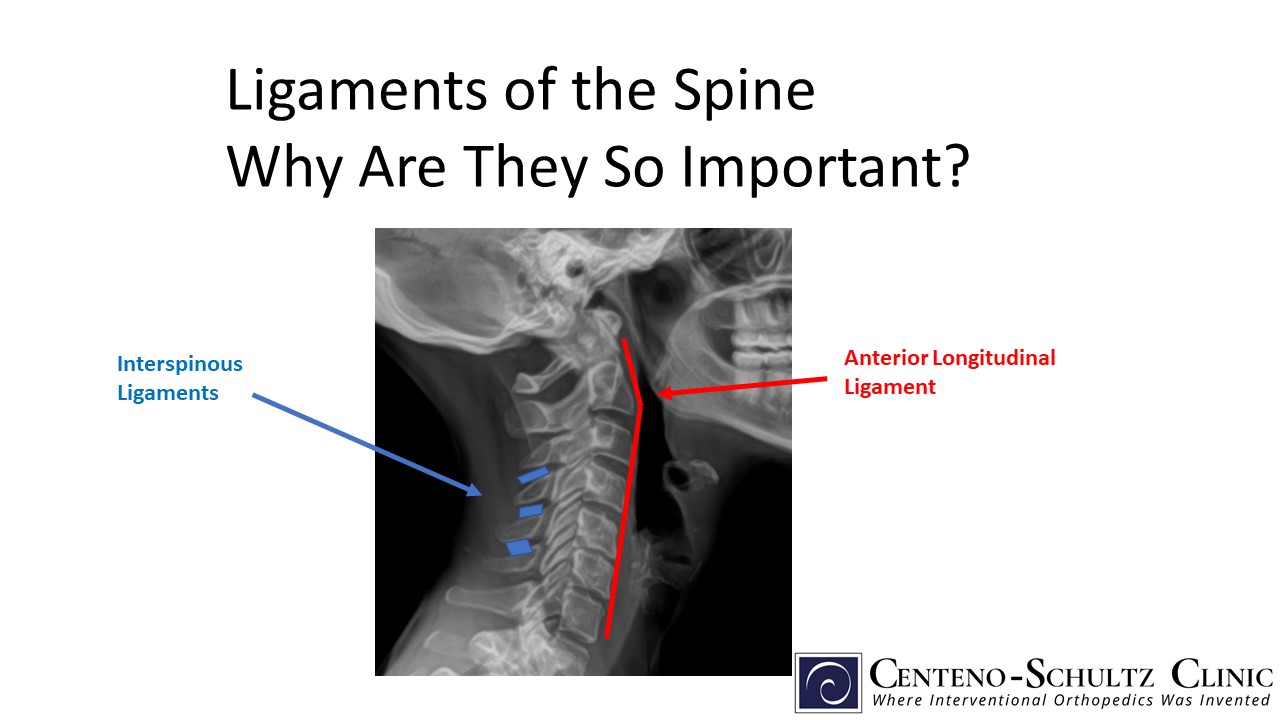

Do You Have Neck Pain? It Could Be Coming From Your Ligaments - Old Post Physical Therapy

Afraid to stick your neck out when it comes to naming cervical spine ligaments? Know the anterior longitudinal ligament (ALL) \u0026 that's ALL? Is the nuchal ligament a NEW CALL for you?